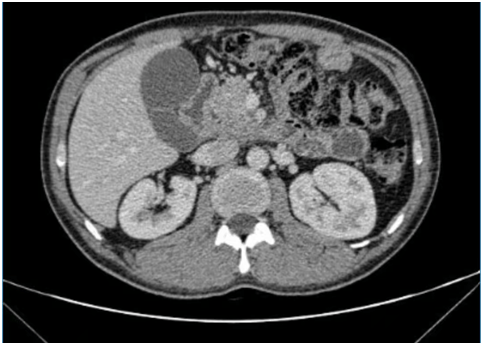

初到医院时,小陈的病情确实棘手。入院CT、MRI提示:胰头颈部胰腺癌并周围侵犯;肿瘤已经包绕侵犯了几支重要血管:门静脉主干、脾静脉、胃左动脉、肠系膜上动静脉、下腔静脉,并且可见病灶周围及肠系膜根部多发淋巴结。陈艳军主任仔细评估后,制定了“先调整,后消融”的策略:先行全身化疗联合免疫治疗,争取控制肿瘤发展,为后续治疗创造可能。

在团队的精心治疗与呵护下,奇迹出现了。多次行化疗和免疫治疗后,复查CT显示肿瘤明显缩小!时机成熟,陈主任当机立断:可以行纳米刀消融术!